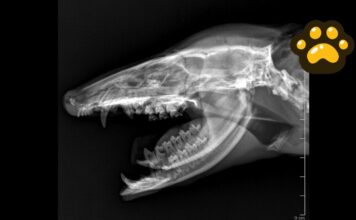

Tlacuache atropellado en Puebla recibe atención; su estado de salud es...

Personal médico veterinario del área de vida silvestre de la Secretaría de Medio Ambiente de Puebla brindó atención a un tlacuache macho de 1.7...